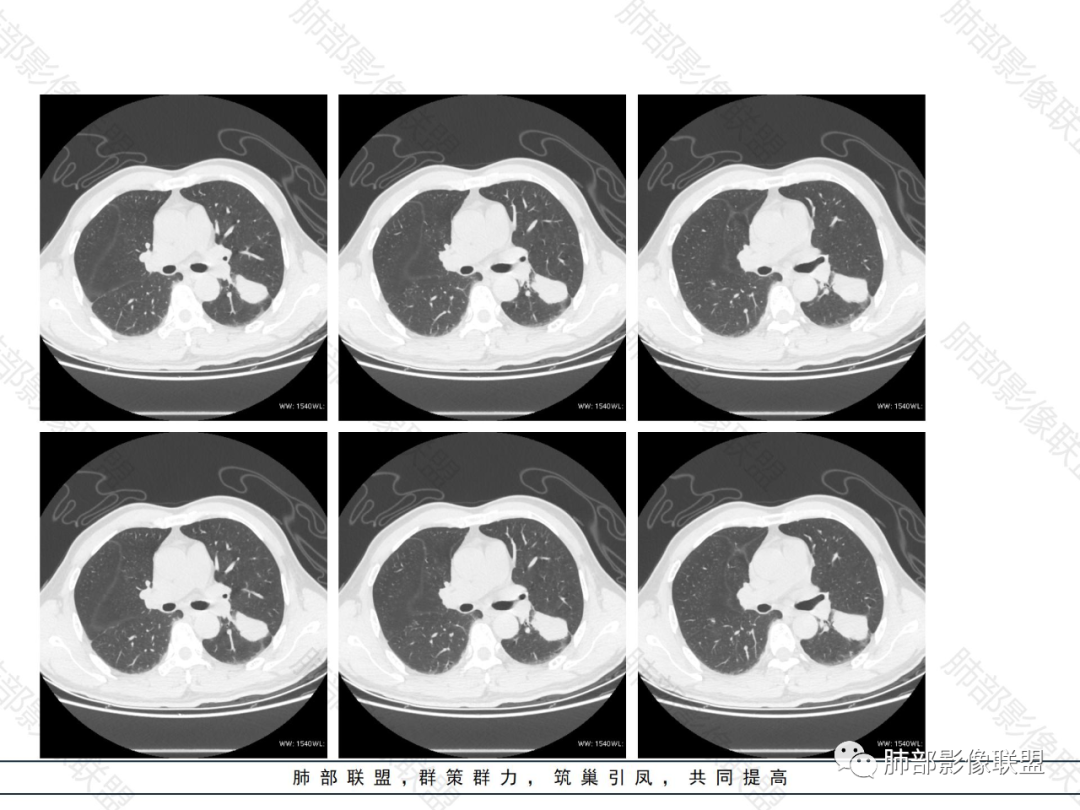

外围胸膜下、支气管血管束分布

实变,密度较均匀

病灶的边缘平直、膨隆都有

内部支气管稍扩张,直达远端,或受压变形、移位

支气管通畅、稍扩张、移位——不支持支气管来源

提示间质来源、周围肺实质来源

占位效应与收缩性均匀,内部支气管稍扩张,或推移,淋巴瘤要考虑

1.病灶分布:因为肺内淋巴瘤主要侵犯对象是肺间质和支气管黏膜下组织,病灶主要位于在沿支气管血管束分布、肺间质及胸膜下,病灶可跨叶分布。

3.支气管充气征伴或不伴支气管扩张:肿瘤细胞沿肺间质及支气管黏膜下组织浸润,支气管管壁未见明显破坏,管腔内未见肿瘤细胞充填,呈现充气支气管征;充气支气管走行自然,无扭曲、僵硬,内壁管腔光滑,支气管管壁见增厚并常有管腔的扩张,含气支气管可呈串珠样不均匀扩张,扩张明显处呈空腔样或皂泡样的囊状含气影;支气管扩张目前有两种意见:一是由于肿瘤组织起源于肺间质,肿瘤沿或跨越脏器解剖结构生长,原有解剖结构残留,周围增生的纤维结缔组织牵拉导致支气管扩张;二肿瘤侵犯支气管粘膜下植物神经丛致平滑肌张力丧失;而这类支气管扩张在肿瘤治疗后有时可消失。

支气管充气征伴扩张

5.病灶的边缘:有膨隆,浅分叶,也有平直、收缩,平直收缩是因为肿瘤组织浸润致肺泡塌陷及周围纤维组织增生,牵拉正常的肺组织向病灶中心形成聚拢状改变,似呈“炎性”改变。

膨隆、平直